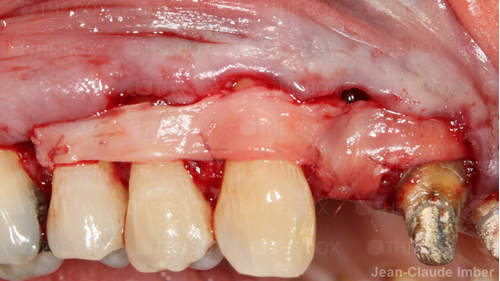

A new case was made public by Jean-Claude Imber check it out here.